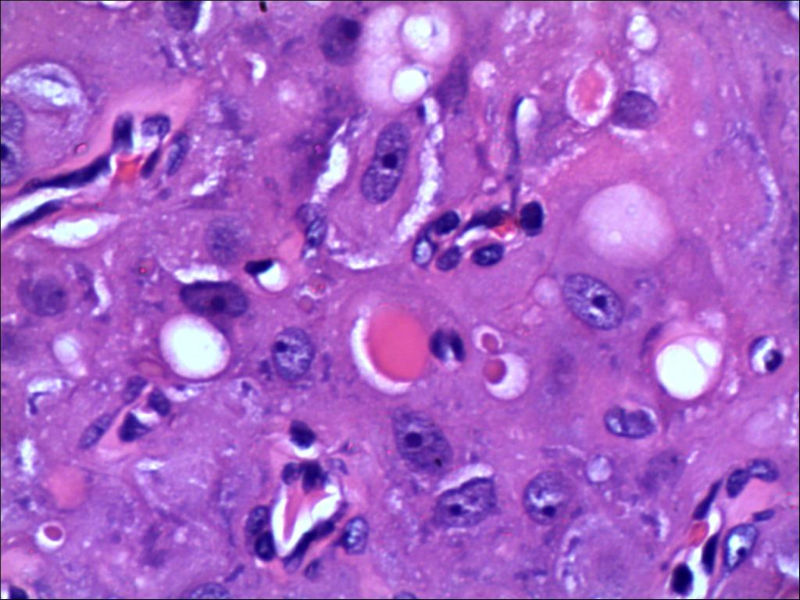

女,27岁,送检右侧卵巢肿物(另外还送检左侧卵巢肿物,大体及镜下显示为畸胎瘤),卵圆形,大小2×1×1cm,似有包膜。卵巢肿物图1

卵巢畸胎瘤中正常卵巢的黄体组织,铺砖样排列,胞浆宽大,较典型。

不好意思,可能是我没说清楚,患者对侧卵巢是畸胎瘤,不是同一侧的,我初步考虑门细胞瘤,图21,22,24,25,26中央的一些细胞是不是很像门细胞

谢谢大家的回答和解疑,忘记一个重要的病史,就是该女性为产妇。但是妊娠黄体瘤与类固醇细胞瘤怎么鉴别呢

那应该是妊娠黄体/黄体瘤,类固醇细胞瘤有嗜酸细胞和组织细胞样细胞两种,此例显然不是。